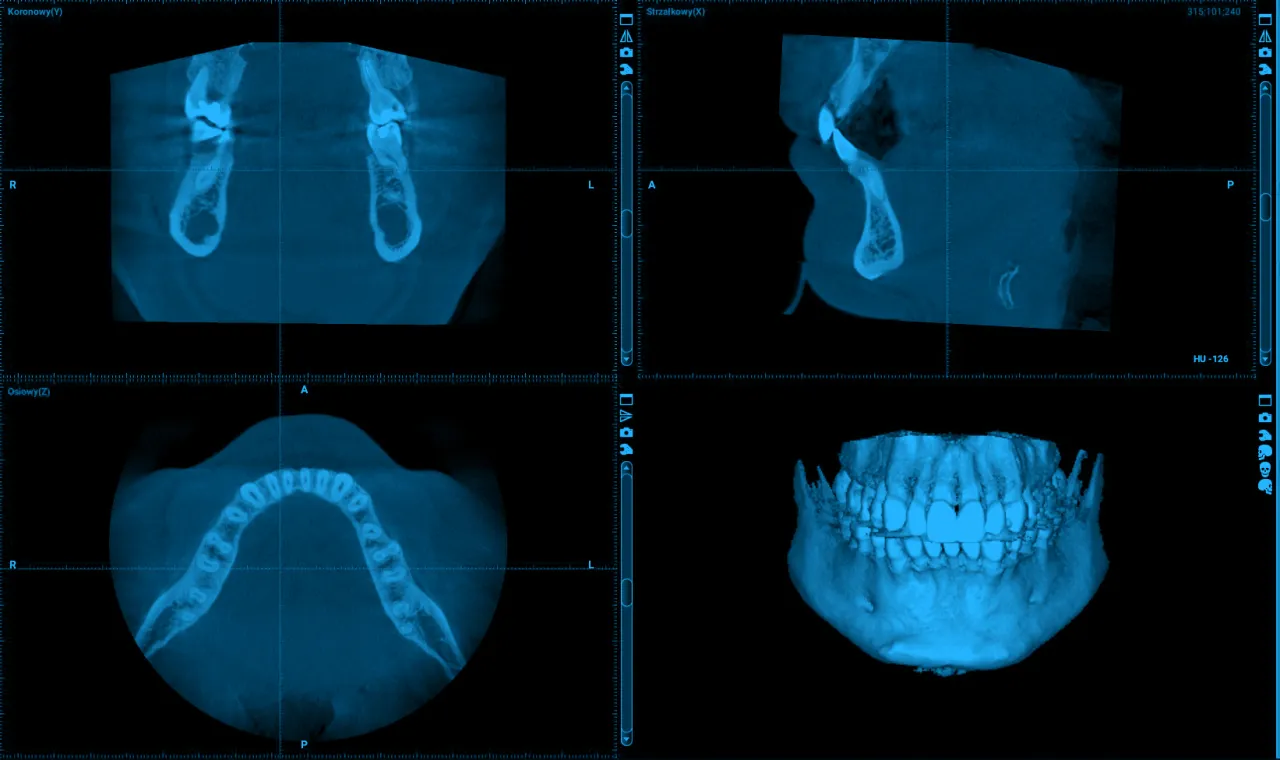

Dlaczego zwykłe RTG to za mało? Rola tomografii CBCT w wykrywaniu pęknięć

Standardowe zdjęcia rentgenowskie (RTG), choć powszechnie stosowane w stomatologii, często okazują się niewystarczające do precyzyjnego zdiagnozowania pęknięcia korzenia. Są one dwuwymiarowe i mogą maskować drobne szczeliny, zwłaszcza te biegnące pionowo wzdłuż korzenia. Dlatego złotym standardem w diagnostyce pęknięć korzeni jest tomografia komputerowa wiązki stożkowej (CBCT). Ta nowoczesna technologia pozwala na uzyskanie trójwymiarowego obrazu zęba i otaczających go tkanek z bardzo wysoką rozdzielczością. Dzięki temu lekarz może niemal ze 100% pewnością ocenić obecność, lokalizację, kierunek i głębokość pęknięcia, co jest kluczowe dla dalszego planowania leczenia.